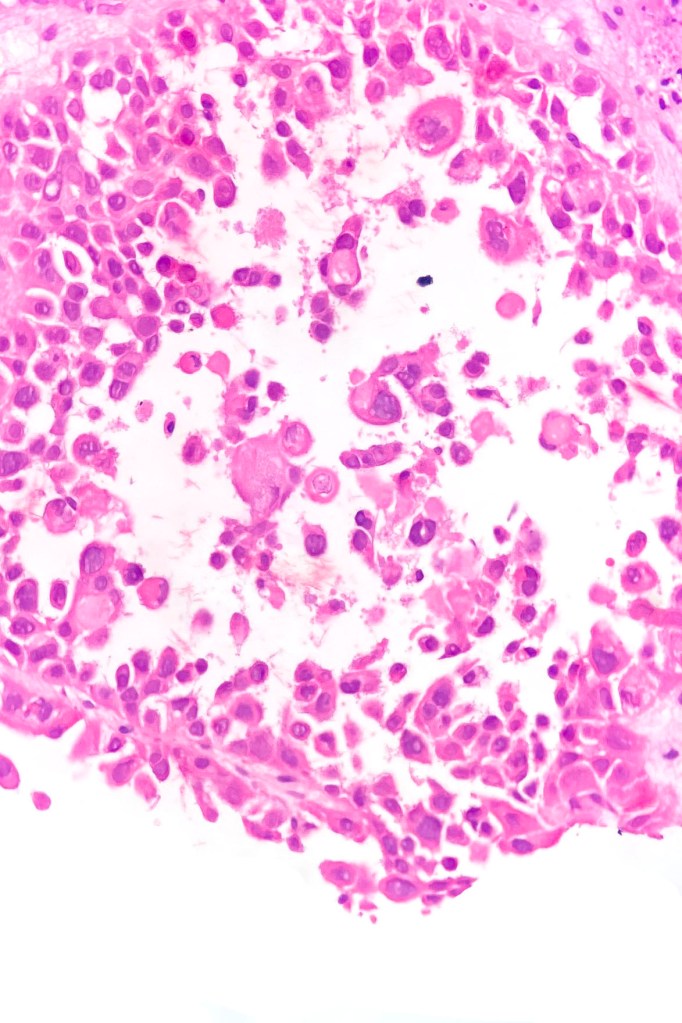

•Acantholysis gives rise to a pseudoglandular appearance

•Variable pleomorphism & mitotic activity

•Exceptional associated signet-ring cell change (signet ring cell squamous carcinoma)

In my experience, acantholytic squamous carcinoma invariably shows foci of more obvious squamous differentiation but if this is not the case, then an adenocarcinoma (particularly metastatic) enters the differential diagnosis. Demonstration of CK7 or CK20, CEA, DPAS, mucicarmine or alcain blue should readily afford their distinction. Exceptionally, melanoma can show a pseudoacantholytic (pseudoglandular) appearance due to excessive stromal mucin deposition.